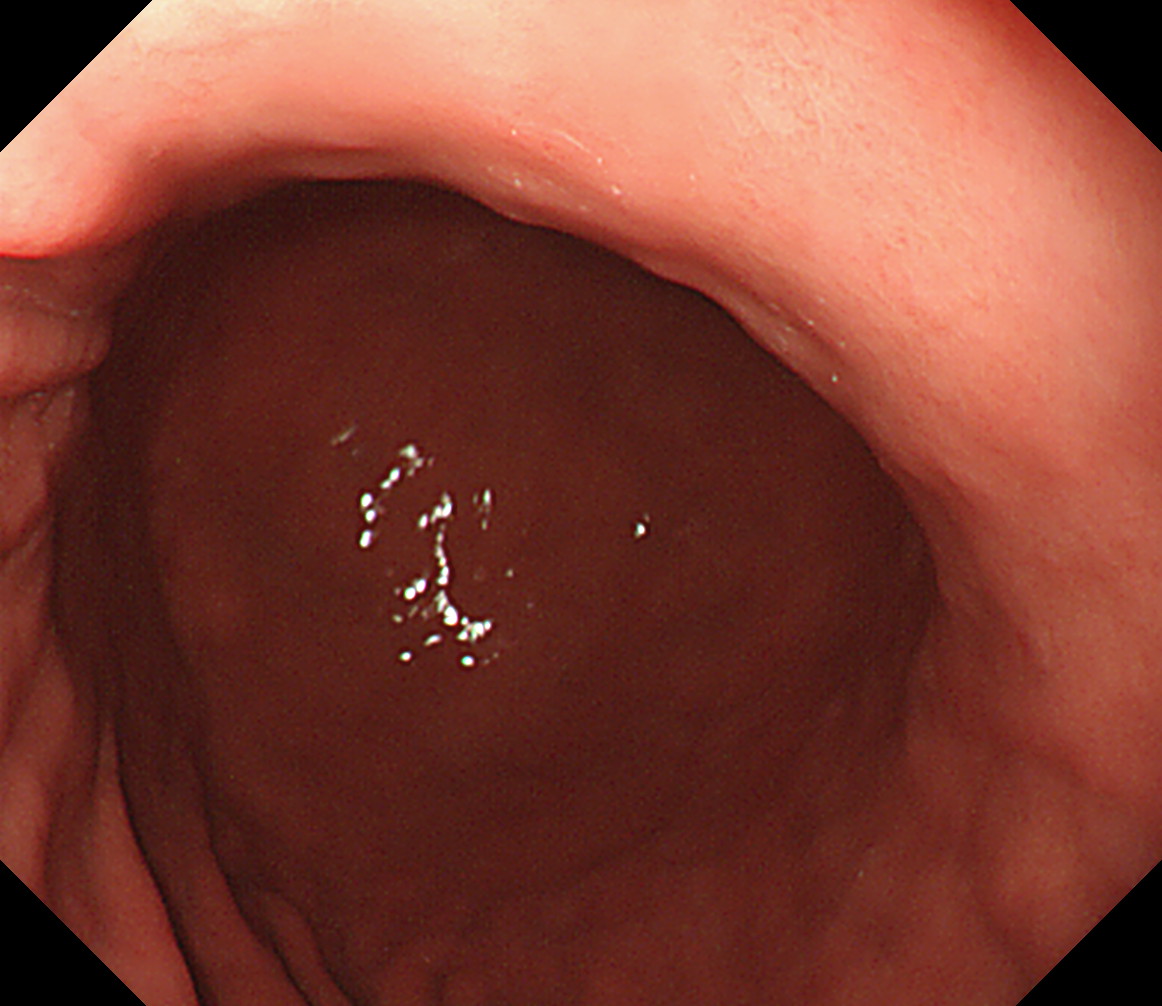

1 食道中部 門歯から約25cm 中部食道

2 食道下部 門歯から約35cm 食道下部